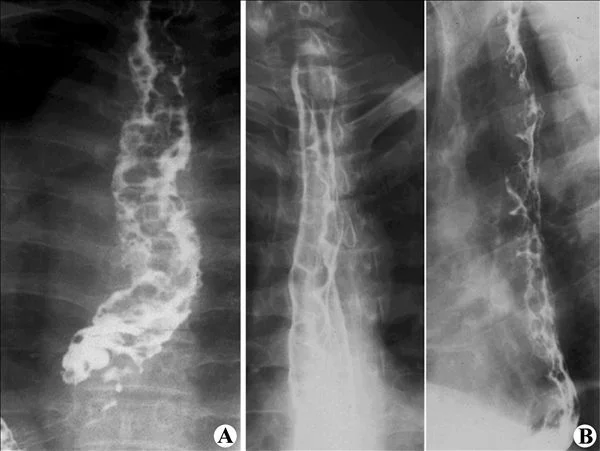

(1) X线检查可确定肿瘤的上、下范围,尤其是双对比造影,对治疗有一定参考居怎居帝剧压老装够责白价值。若要根据食管的扩装抗下展性来判断病源范围、来自食管周围的侵蚀及淋巴结转移和疾病分期,则必须依靠CT检查。 (2) 食管异物检查首先应透视颈部及胸部,以观察是否有不透X线的异物存留,然后可口服浸以钡剂的棉花球,如棉花球停留在一个固定部位而不再下降时,型响质段利应怀疑有异物存在的可能。此法对鸡骨或鱼骨刺有效,但有时有假阳性,应结合患者的病史及食管镜检查进行最后确诊。 (3) 气钡双重对比造影,可清晰显示食管黏膜结构。